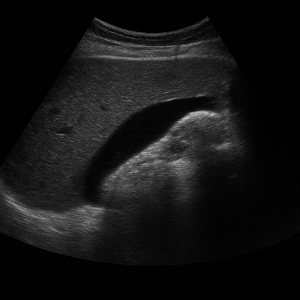

반사와 신호 수신

초음파가 배 안 장기나 조직에 부딪히면 일부는 반사되어 돌아오고, 이 반사파를 탐촉자가 받아 전기 신호로 바꿔요. 컴퓨터가 이 신호를 이용해서 화면에 영상으로 보여줍니다 .

이미지 생성

영상이 만들어지는 원리는 시간(반사파가 돌아오는 속도)과 강도(얼마나 세게 반사되었는지)를 컴퓨터가 계산해 이미지의 위치와 밝기를 결정하는 방식이에요. 깊이가 깊을수록 반사되는 시간도 길어지고, 반사파가 세면 화면에서 밝게 나타나요 .